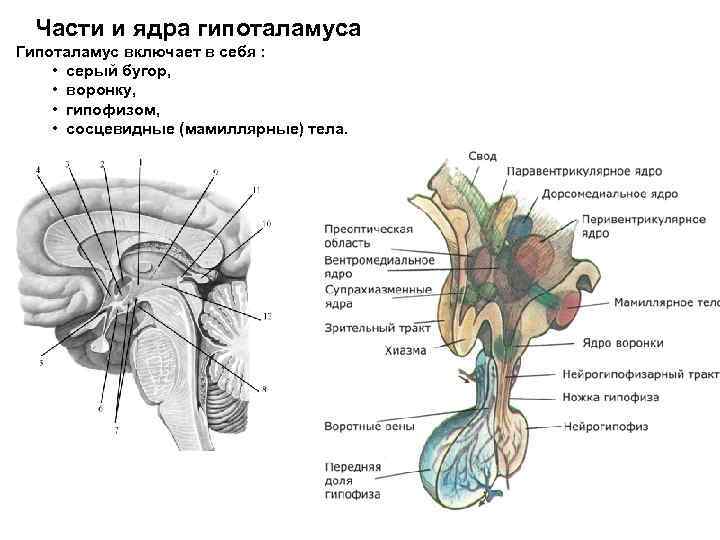

Необычные объекты: Переднее продырявленное вещество

Раздел: Альбом открытий